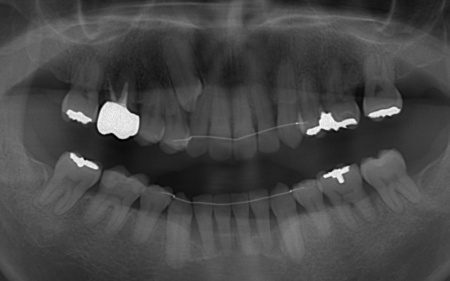

またレントゲン撮影をして確認すると、右上前歯は顎の骨の中に埋まっている骨性埋伏(こっせいまいふく)の状態でした。

本来、骨性埋伏の歯は、歯茎を切開して中の歯を引っ張る開窓牽引(かいそうけんいん)を行うのが一般的ですが、患者様の歯は骨の中に深く埋まっていたため、開窓牽引は難しいと考えられます。

さらに、左下奥歯は重度の歯周病であり、歯を支えている骨が一部溶けていることが判明しました。

このまま放置すると骨がさらに溶け、歯を残すことが難しくなるおそれがあります。

今回のケースでは、左上下の奥歯各1本(第3大臼歯)、右下の奥歯1本(第3大臼歯)、左上下と右下の奥歯各1本(第1小臼歯)の計6本の抜歯が必要です。

骨に埋まっている右上前歯は引っ張り出すことができないため、隣の歯である右上奥歯(第1小臼歯)を代用歯として機能させる方法を選択しました。